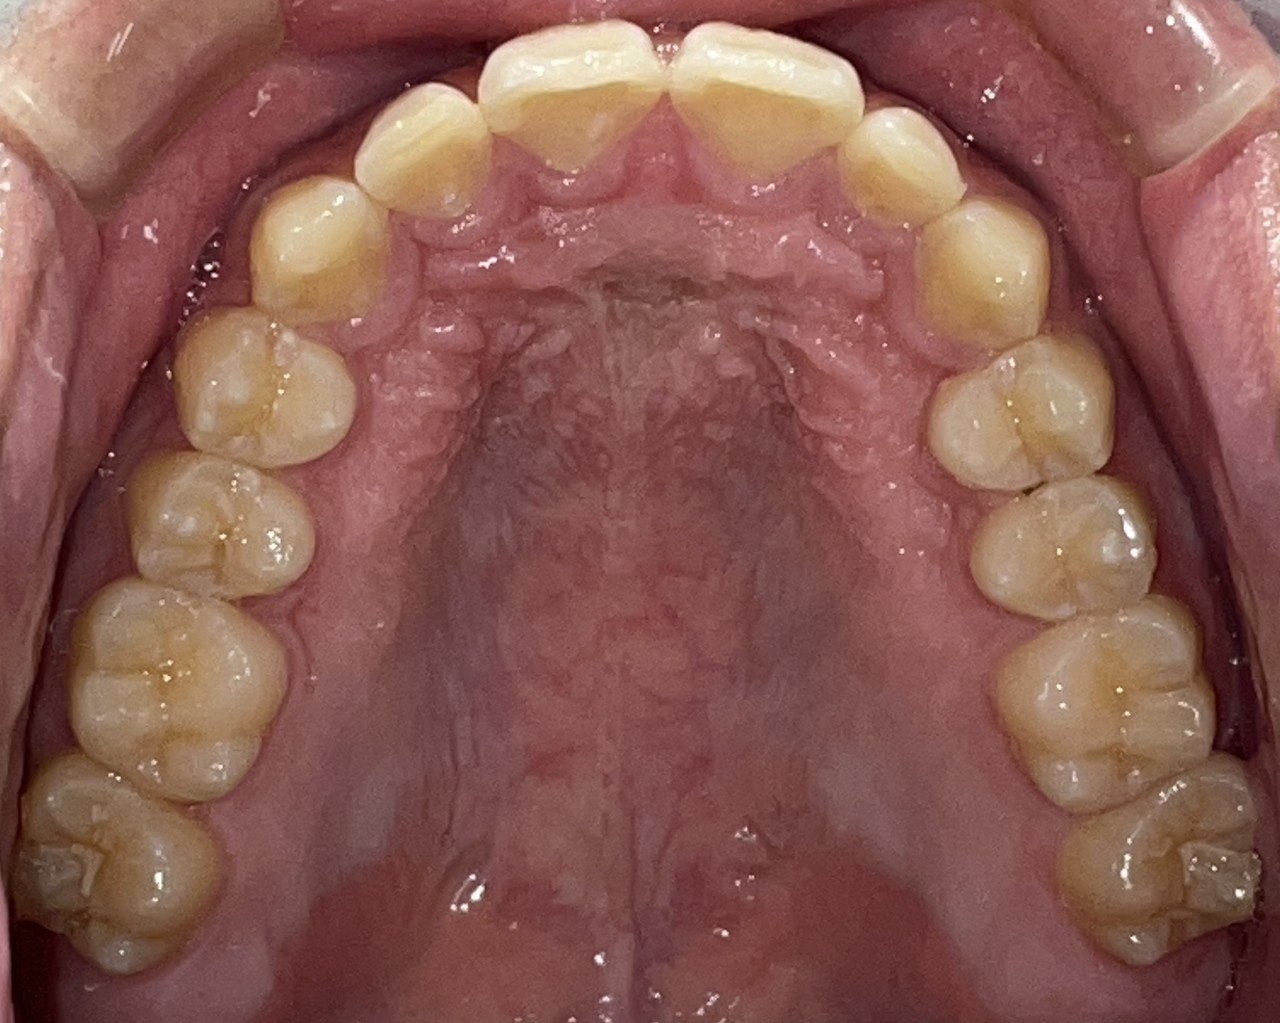

Before

After

矯正の種類 / invisalign GO

年齢・性別 / 30代男性

主訴  /  下の歯の叢生、オーバージェット、交叉咬合

治療期間 / 12ヶ月

費用 / 簡易検査 5,000円(税別) 精密検査 30,000円(税別)

両額マウスピース 450,000円(税別) 両額リテイナー料 40,000円(税別)

※マウスピース交換時別途調節料5,000円(税別)

副作用 / 口内炎・歯の移動に伴う痛み・知覚過敏 ※数日で収まる場合が多いです

リスク / 後戻り防止の為、夜のみマウスピースで保定を指示